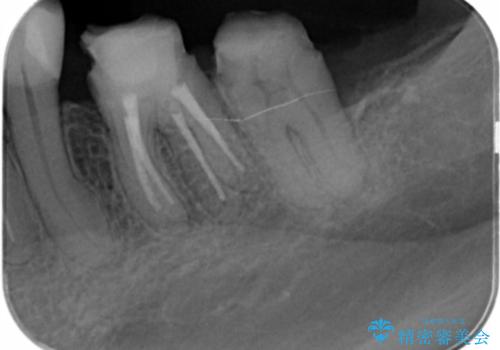

銀歯を除去したのち、虫歯を丁寧に除去し、歯を残せるのかどうかをしっかりと評価し、長期的な予後を見据えた虫歯治療を行っていきます。

銀歯の下で虫歯が再発していた歯は、無理に残しても割れてしまう可能性が非常に高いと考えたため、相談の上抜去を行いインプラント治療を行っていくこととしました。